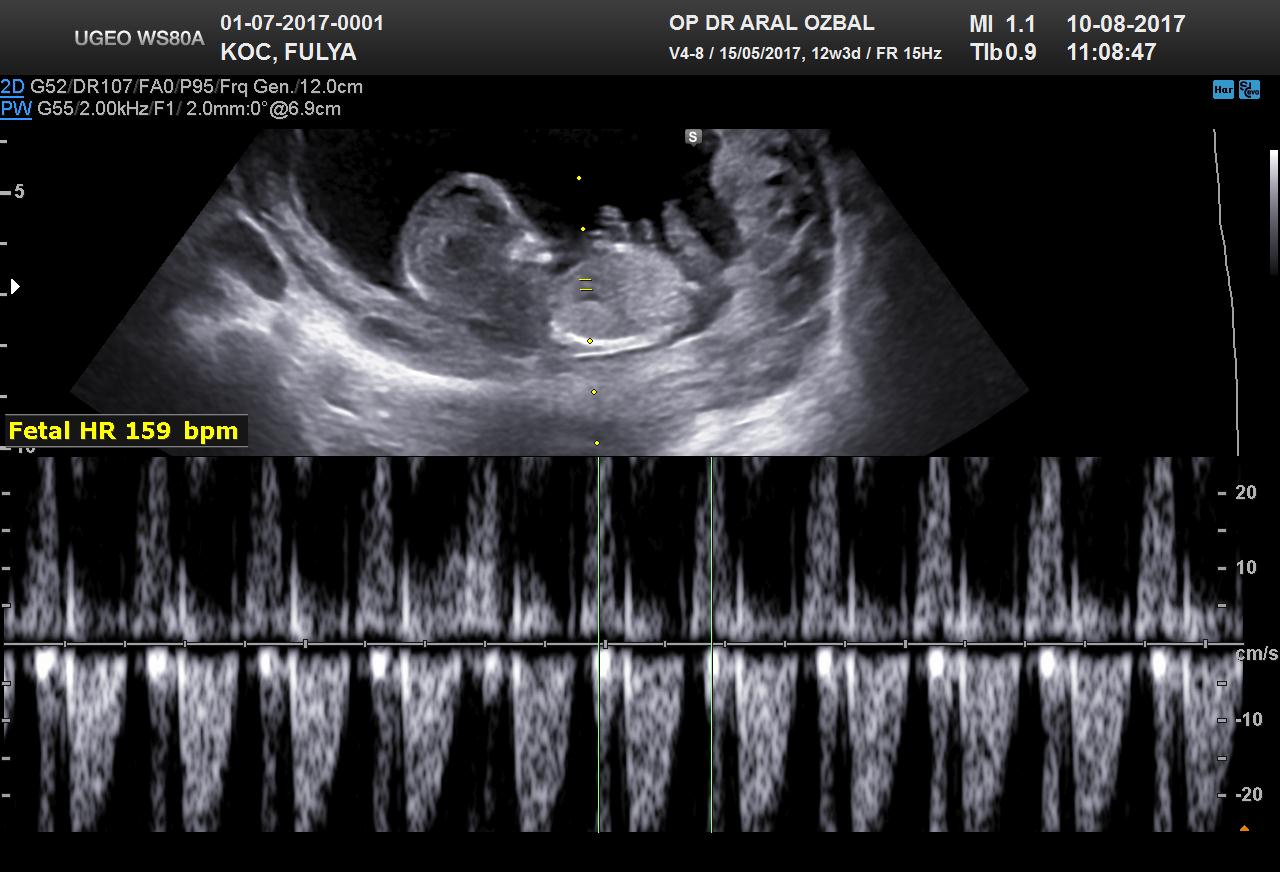

B Baharr@86 Forum Okuru 14 Ağustos 2017 #27 Benimkinede bakabilirmisiniz. 12+3 haftalık Ekli dosyalar 20170810111903_967.jpg 94,5 KB · Görüntüleme: 946 20170810111903_390.jpg 69,9 KB · Görüntüleme: 927

Uzman SühaN Administrator 14 Ağustos 2017 #28 Merhaba nub teorisine göre bebeğin poziyonu yan olmalı . Uygun görsele sahip değilsiniz bu yüzden değerlendirme yapamıyoruz.

Merhaba nub teorisine göre bebeğin poziyonu yan olmalı . Uygun görsele sahip değilsiniz bu yüzden değerlendirme yapamıyoruz.